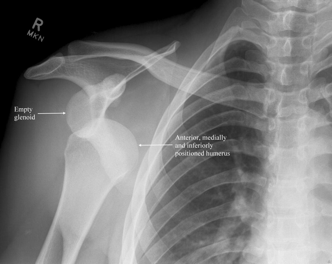

What type of dislocation would cause sensory loss of deltoid and weak abduction of the shoulder? Explain why

Anterior shoulder dislocation

Commonly injures axillary nerve which runs below humeral head and wraps around neck